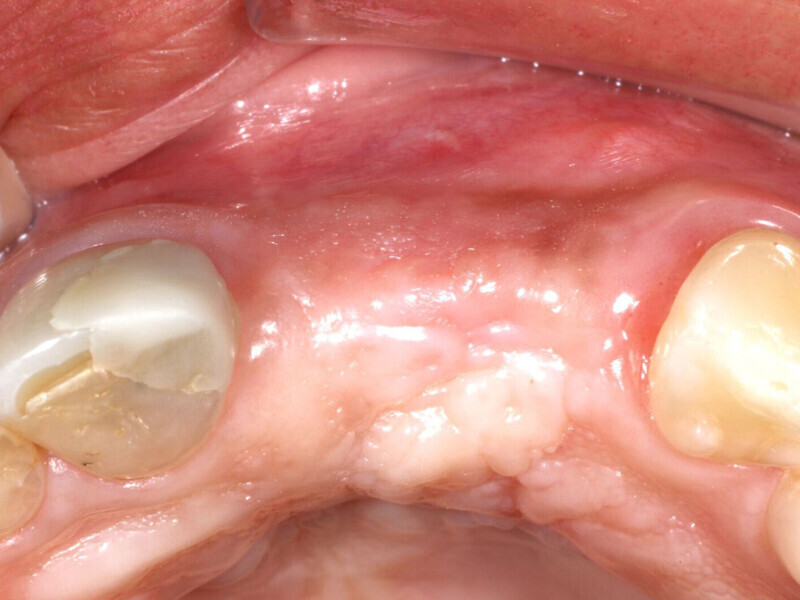

Fig. 1: Deficient facial aspect to the anterior maxilla resulting from resorption following tooth extraction. (Photos provided by Dr. Arun K. Garg; Dr. Gregori M. Kurtzman; Dr. Renato Rossi Jr.; and Dr. Maria del Pilar Rios)